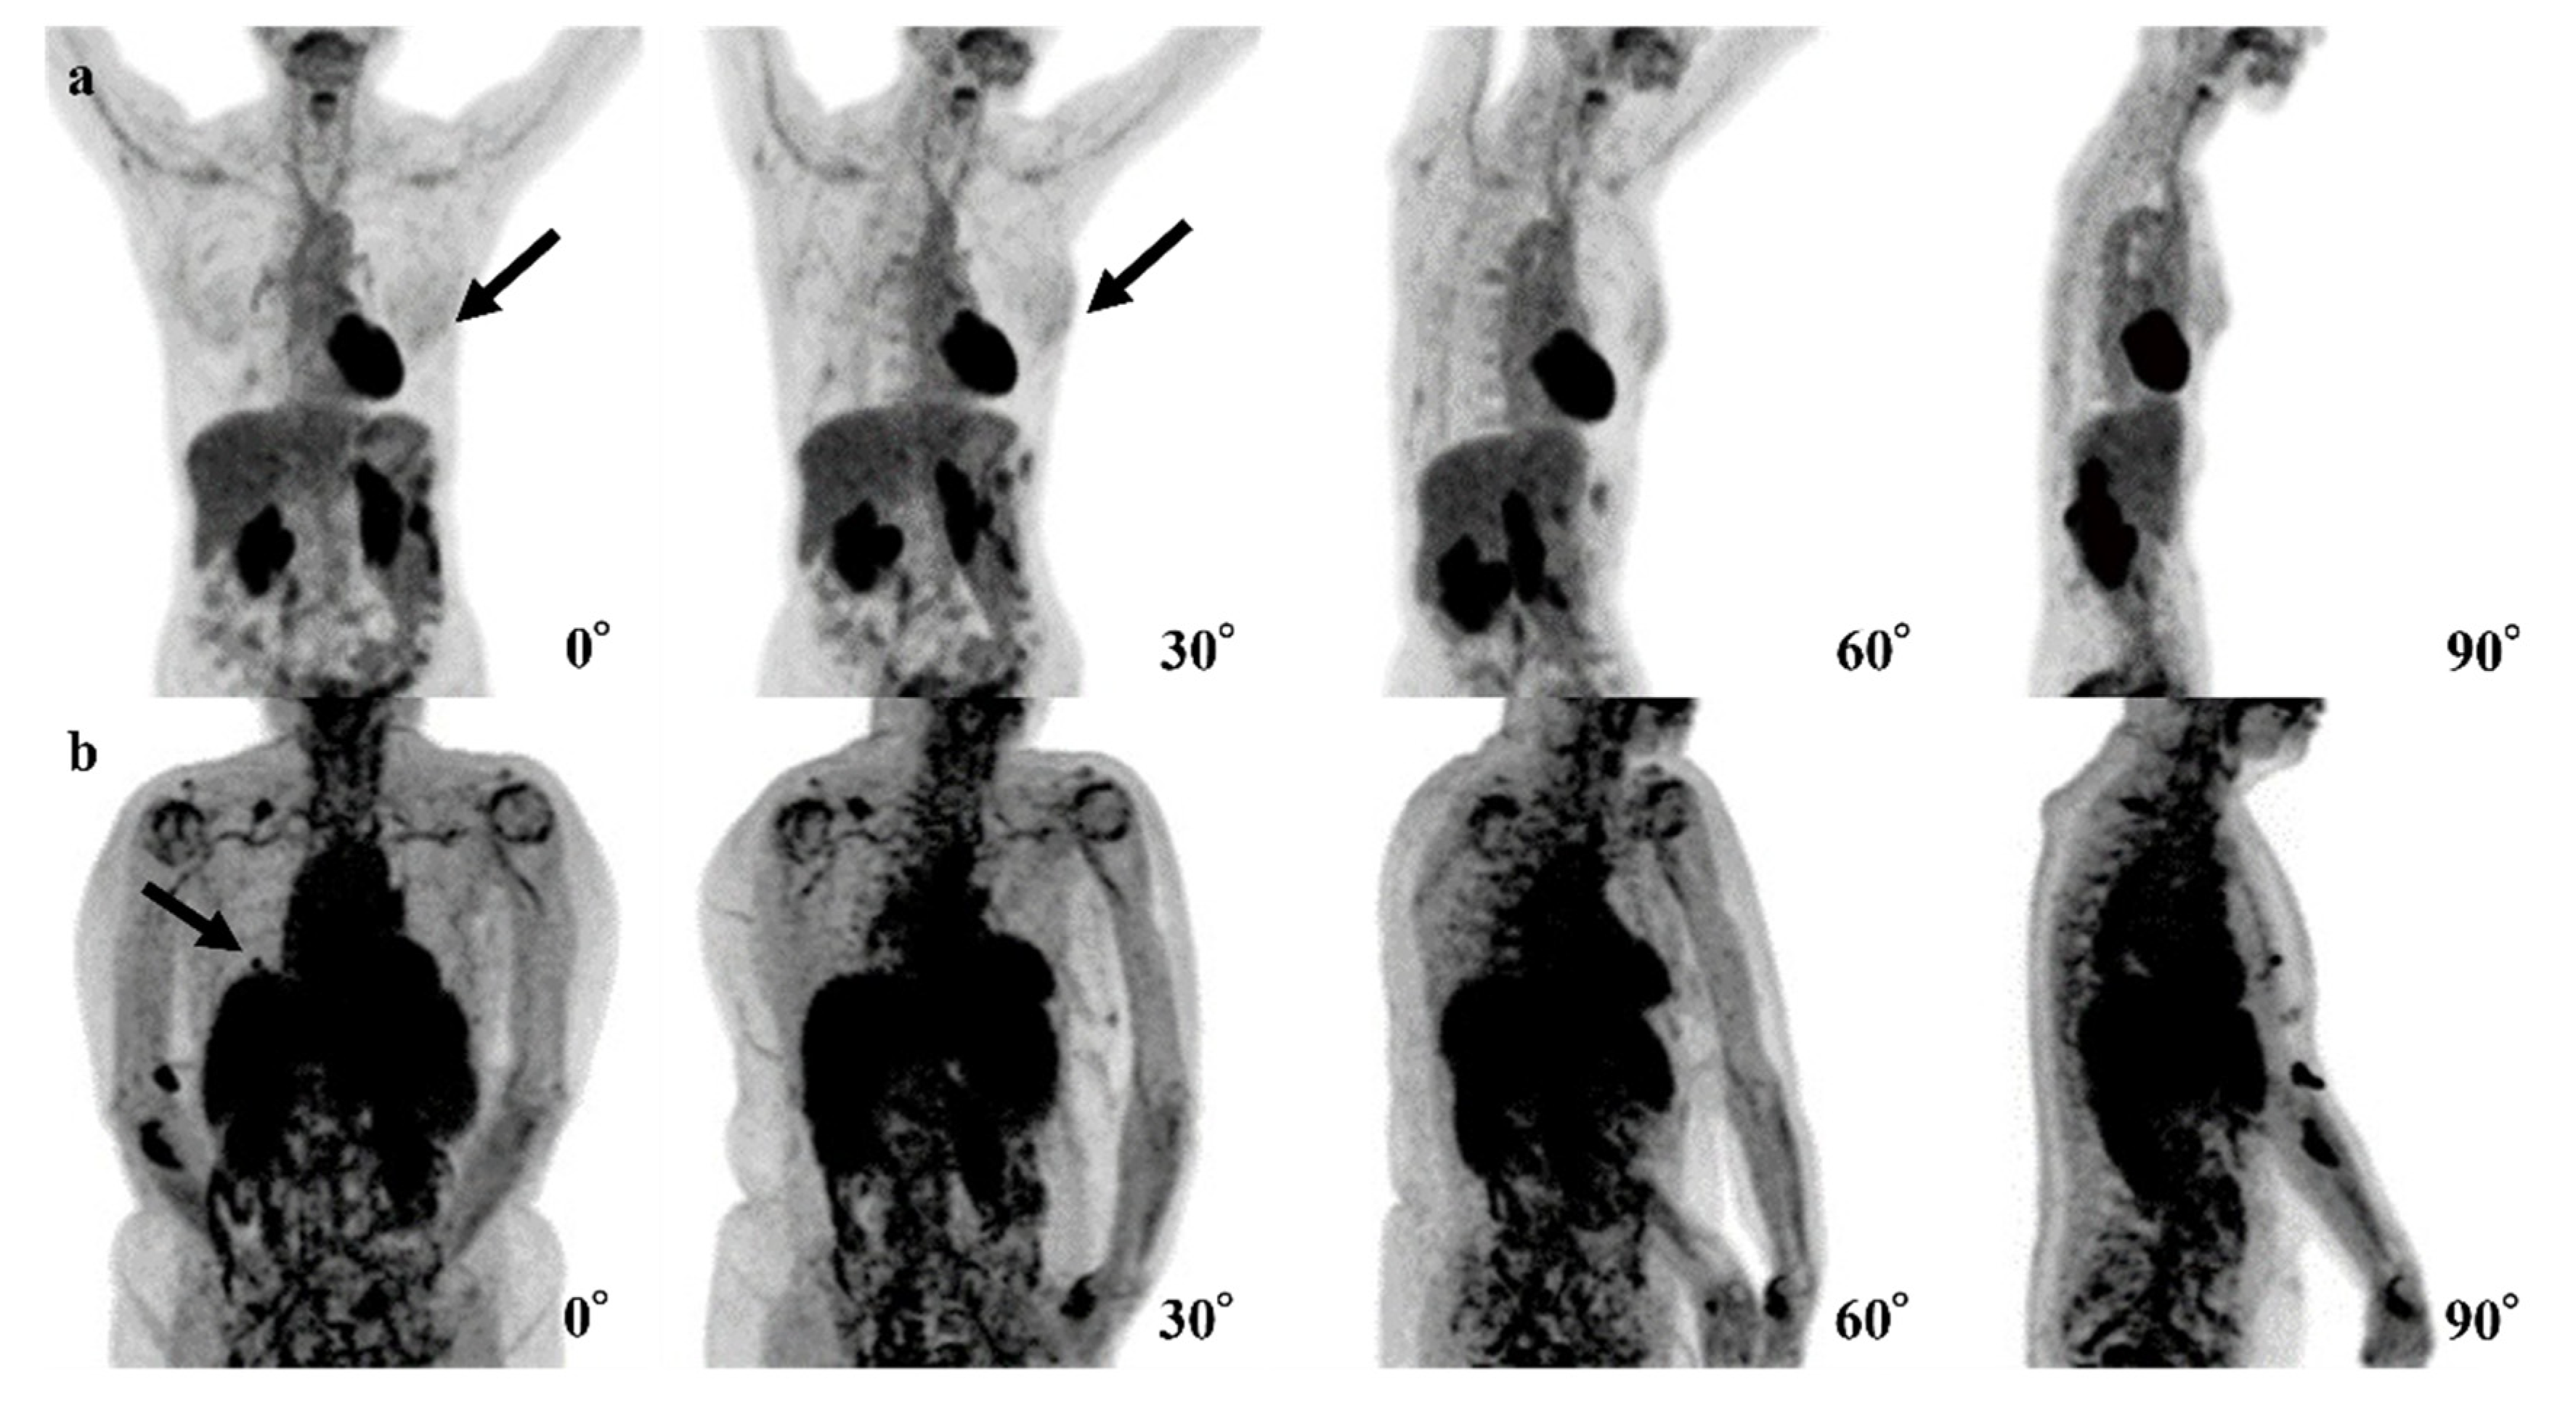

| Case | Age | SUVmax | Breast Density | Size of Invasive Components (mm) | Total Tumor Size (mm) | Pathology and Subtype | ER | PgR | HER2 | Ki67 |

|---|---|---|---|---|---|---|---|---|---|---|

| 1 | 44 | 2.0 | Heterogeneously | 11 | 11 | IDC | + | + | - | 9.1% |

| 2 | 70 | 0.9 | Scattered | None | 0.6 | DCIS | + | - | + | 15.4% |

| 3 | 70 | 1.2 | Heterogeneously | None | 8 | DCIS | + | + | + | 12.0% |